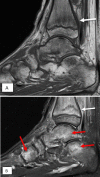

Figure 14.

14-year-old boy involved in multiple sports presents with worsening ankle pain. (A) Sagittal T1 and (B) T2FS images of the ankle demonstrate linear signal abnormality in the distal tibia consistent with stress fracture (white arrow). Multiple additional areas of signal abnormality (red arrows) are also consistent with stress reaction.